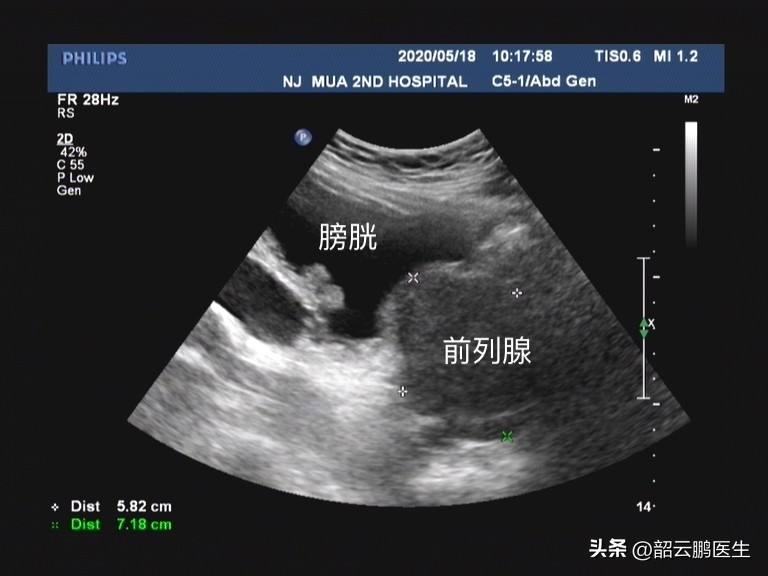

目前临床上前列腺增生的中成药种类很多,但纵观几种我们在临床上较为常见的中成药比如 癃清片和灵泽片,在功能主治中都重点描述了清热泻火,利尿通淋的功效 。那是否对前列腺增生患者合适呢?